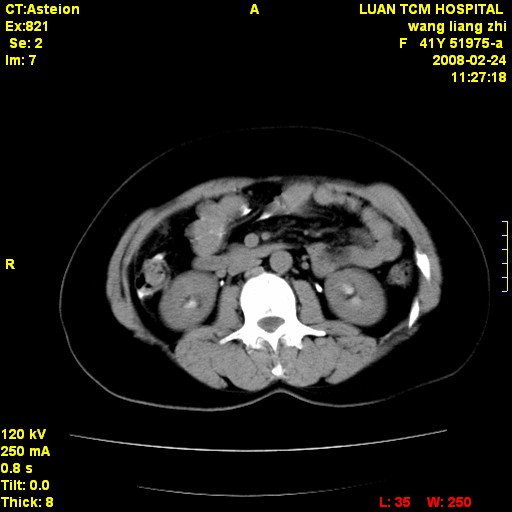

以下是引用dyqct在2009-8-23 16:17:00的发言:[br]考虑:1、造影剂进入腹腔、结肠旁沟、肝周;[br] 2、子宫明显增大(腺肌增生症?);[br] 3、膀胱显影是由于造影剂吸收后经肾分泌进入膀胱的;[br] 4、建议mri检查子宫。